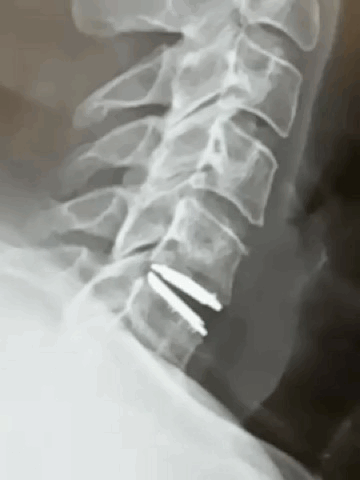

Prodisc C Vivo Cervical Artificial Disc

The Prodisc C Vivo is a keel-less cervical total disc replacement by Centinel Spine. The Prodisc family of discs come in 4 versions: C Vivo, SK (small keel), Nova, C. The disc is a titanium metal-on-poly design with anatomic convex superior endplate and titanium plasma sprayed coating. The endplates are composed of CoCrMo (Cobalt-28Chrome-6Molybdenum) with titanium plasma sprayed coating. The inlay is UHMWPE. The Prodisc Vivo and SK recieved 2 level approval 10/2025

• Keel-less design

• 17 degree flexion and extension, 17 degrees lateral bending, unconstrained axial rotation